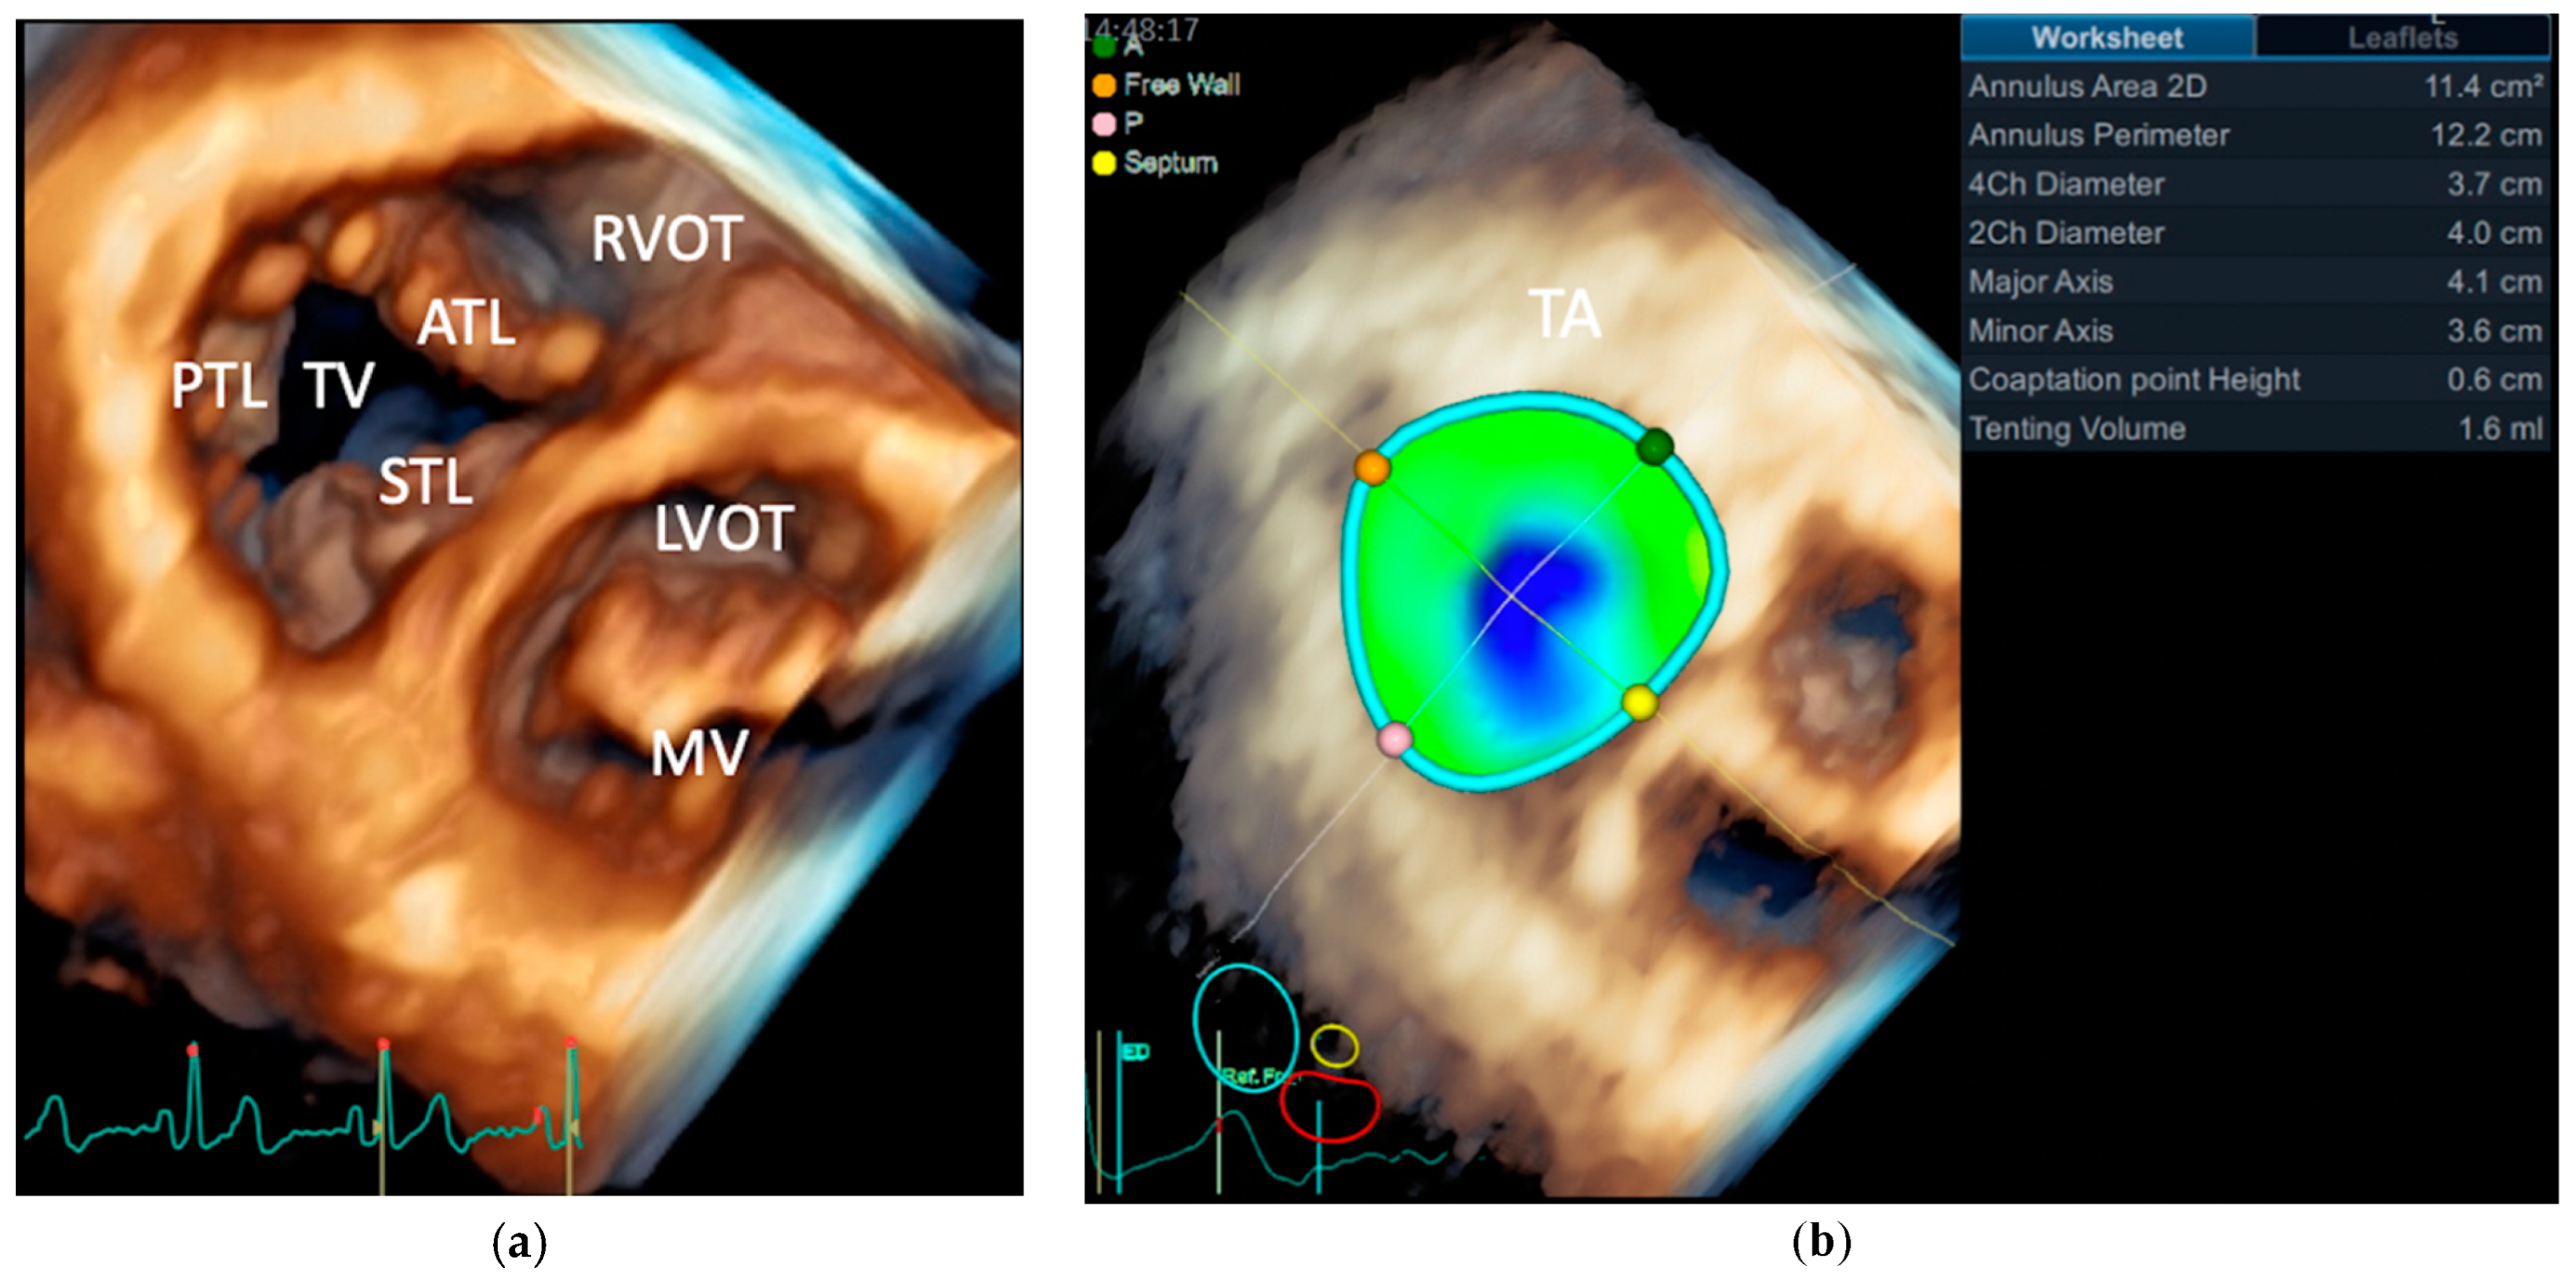

- Muraru, D.; Hahn, R.T.; Soliman, O.I.; Faletra, F.F.; Basso, C.; Badano, L.P. 3-Dimensional Echocardiography in Imaging the Tricuspid Valve. JACC Cardiovasc. Imaging 2019, 12, 500–515. [Google Scholar] [CrossRef]

- Muraru, D.; Badano, L.P.; Sarais, C.; Soldà, E.; Iliceto, S. Evaluation of tricuspid valve morphology and function by transthoracic three-dimensional echocardiography. Curr. Cardiol. Rep. 2011, 13, 242–249. [Google Scholar] [CrossRef]

- Addetia, K.; Muraru, D.; Veronesi, F.; Jenei, C.; Cavalli, G.; Besser, S.A.; Mor-Avi, V.; Lang, R.M.; Badano, L.P. 3-Dimensional Echocardiographic Analysis of the Tricuspid Annulus Provides New Insights Into Tricuspid Valve Geometry and Dynamics. JACC Cardiovasc. Imaging 2019, 12, 401–412. [Google Scholar] [CrossRef]

- Badano, L.P.; Hahn, R.; Zanella, H.; Araiza Garaygordobil, D.; Ochoa-Jimenez, R.C.; Muraru, D. Morphological Assessment of the Tricuspid Apparatus and Grading Regurgitation Severity in Patients With Functional Tricuspid Regurgitation: Thinking Outside the Box. JACC Cardiovasc. Imaging 2019, 12, 652–664. [Google Scholar] [CrossRef]